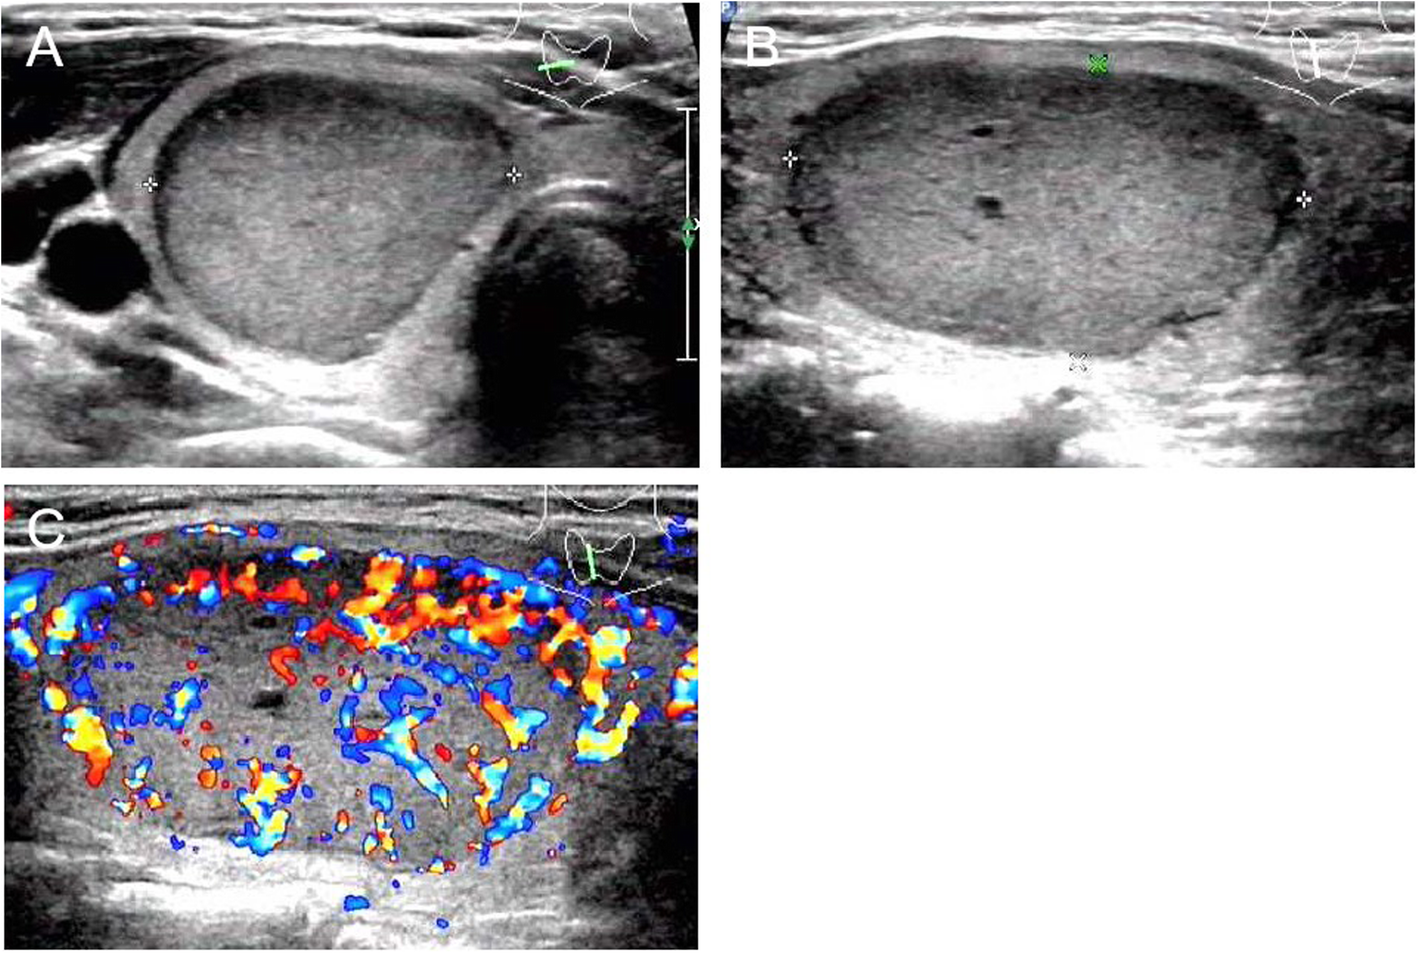

Fig. 4

From: Ultrasound features of medullary thyroid cancer as predictors of biological behavior

US images of medullary thyroid carcinoma nodules categorized by TI-RADS 2. Female patient, 32 years old, 3.8 cm × 2.7 cm × 2.2 cm. The serum calcitonin level was > 2000 pg/mL. a and b Lesion was solid, iso- to hypoechoic echogenicity, well-defined, ovoid shape, small anechoic zone. a A/T < 1. c Enhanced blood flow